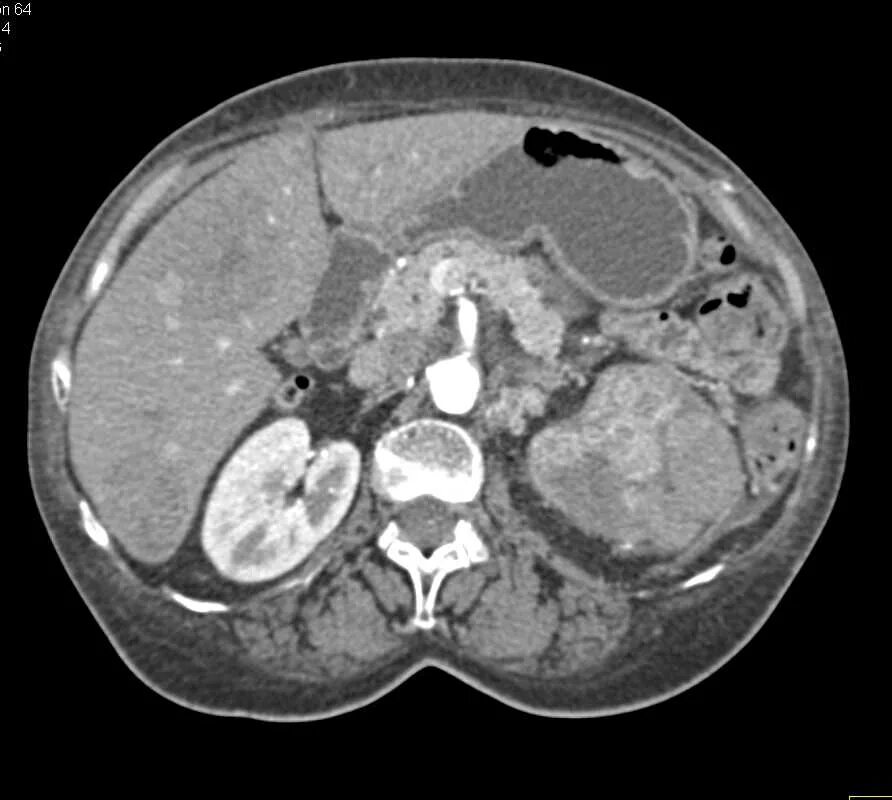

Метастазы рака почки